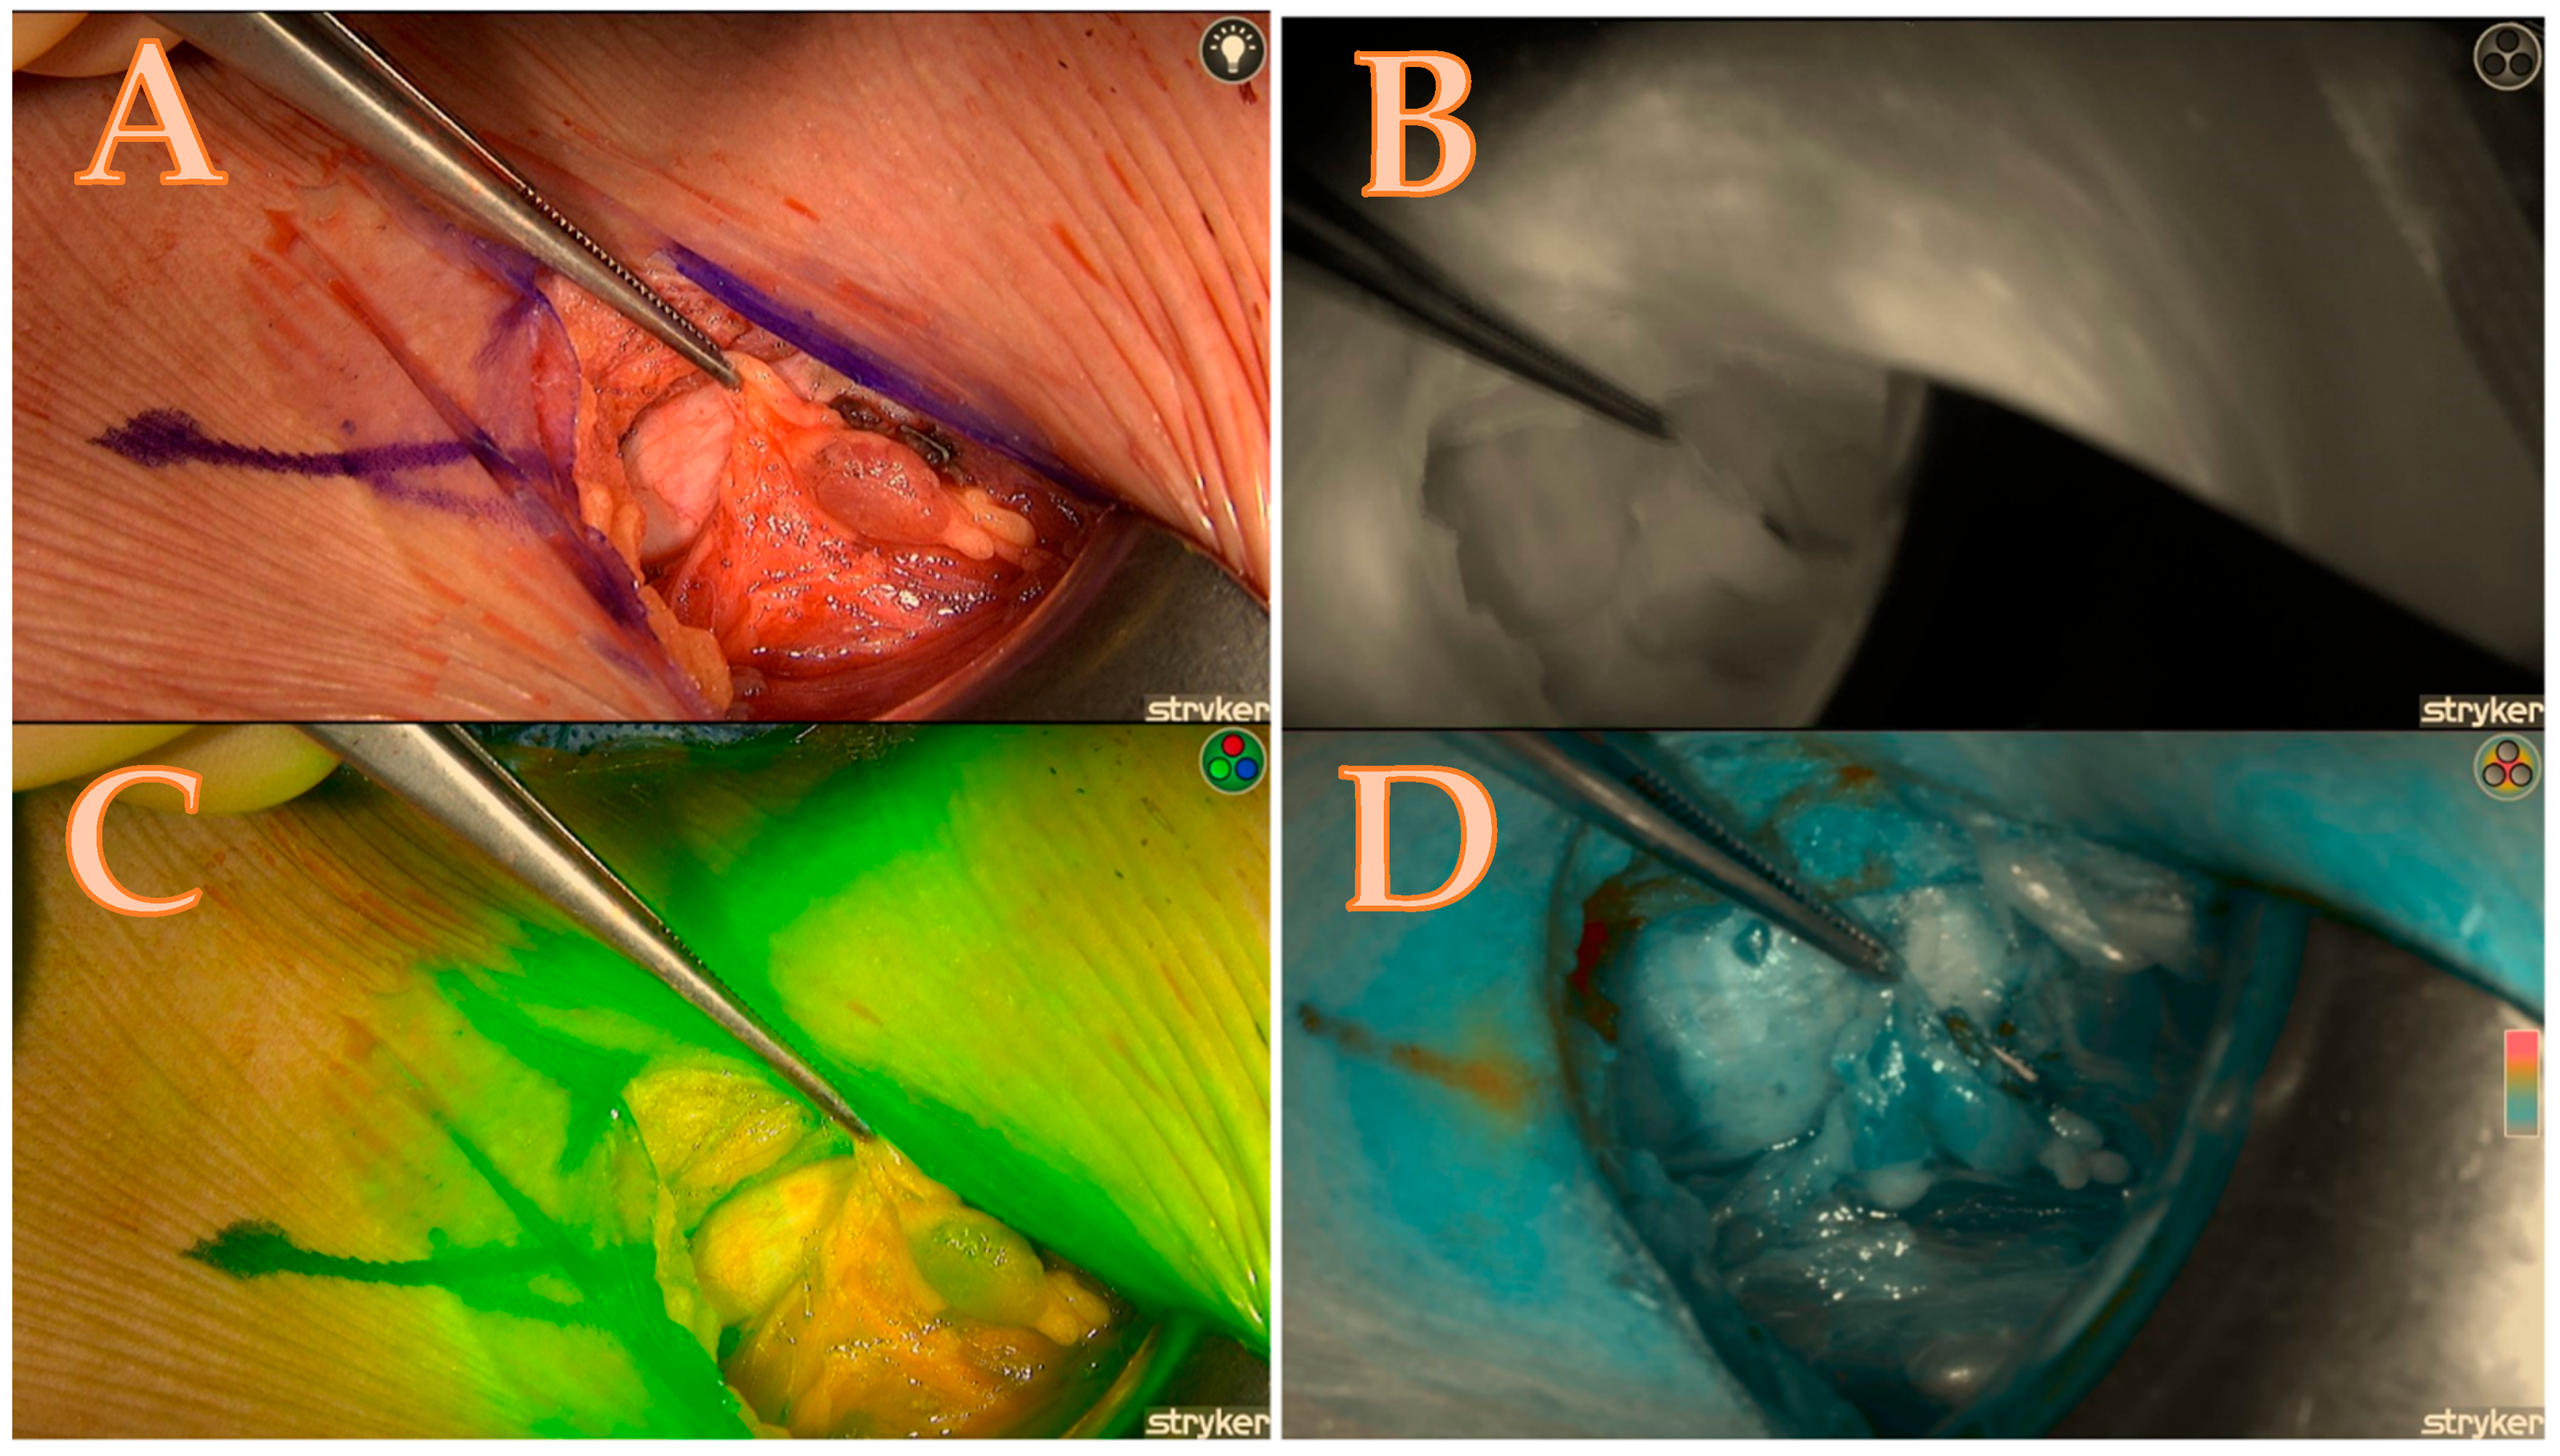

Once a sufficient amount of ICG dye is delivered into the parathyroid gland, it becomes visible as a white fluorescent structure (Figure 2B).

Figure 2.

Both right-sided parathyroids; (A) = native image. The yellow circle depicts the upper parathyroid that remains attached to the thyroid capsule, while the blue circle signifies the lower parathyroid that has become lodged in the capsule. (B) = good brightness of the ICG black-and-white mode illustration of the lower parathyroid and its vascular pathways; (C) = native picture of both parathyroids after right lobectomy; (D) = excellent black/white brightness of the ICG illustration of the lower gland (2 points); moderate inhomogeneous brightness of the upper gland (1 point); (E) = good green mode of the upper gland (2 points); moderate inhomogeneous brightness of the lower gland (1 point). (F) = good colour brightness of the ICG depiction of the lower gland (2 points), moderate inhomogeneous brightness of the upper gland (1 point), total gland score of 11 of a maximal score of 14 displayed in Table 1.

The ability to alternate between the three fluorescence modes, namely black/white, green, and coloured mode, in the Spy-phi imaging system aids in accurately determining the actual intensity of ICG concentration retained within the gland. The homogeneity of the distribution is not only of significant relevance but the colour mode also specifically displays the true intensity from which the Burjeel score is derived, as follows: The colour grey indicates a lack of concentration of ICG in the gland, resulting in a score of zero. The colour blue indicates a moderate concentration of ICG, resulting in a score of one. The colour red or orange indicates an excellent concentration of ICG in the gland, resulting in a score of 2 (Figure 3C).

Figure 3.

Right upper parathyroid; (A) = native image, (B) = the maximum brightness of the ICG illustration in black-and-white mode, (C) = the maximum brightness of the ICG illustration in coloured mode, (D) = the maximum brightness of the ICG illustration in green mode; a total score of 7/7.